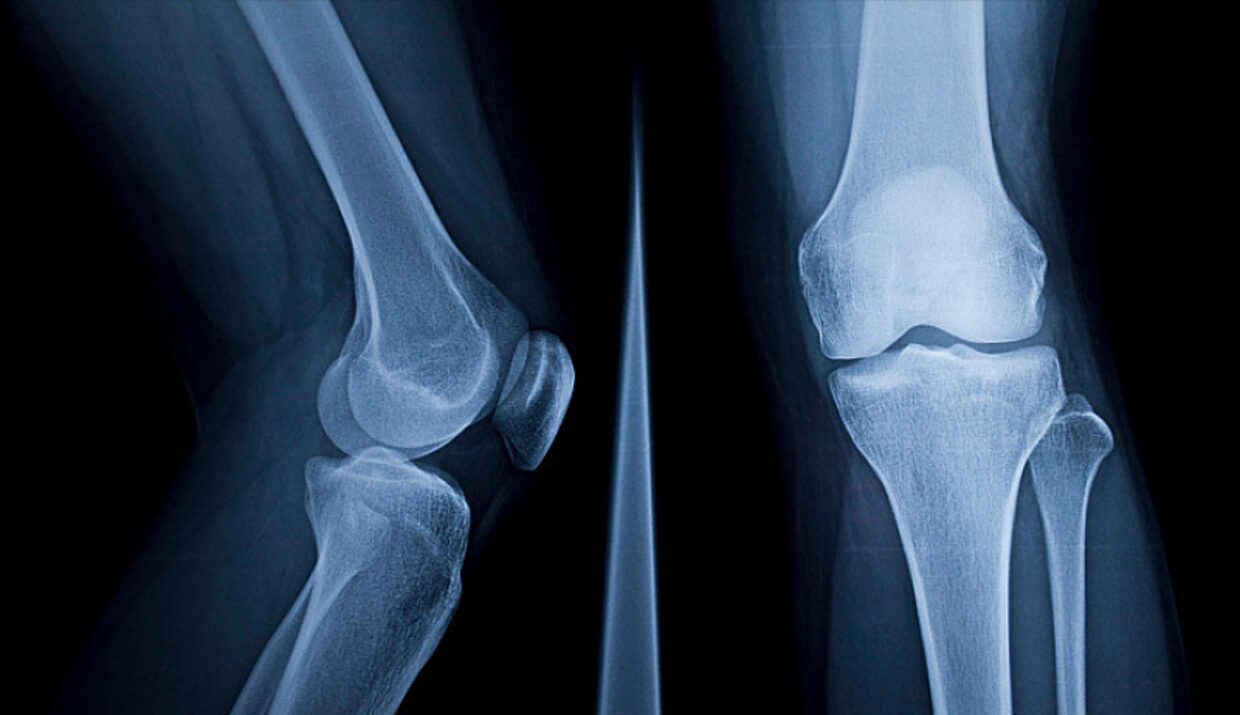

Система с изкуствен интелект, която може да прогнозира как ще изглежда рентгенова снимка на коляното в бъдеще, би могла да промени начина, по който се лекуват милиони пациенти с остеоартрит, пише BBC.

Изследователи от Университета в Съри съобщиха, че разработена от тях технология използва машинно обучение, за да визуализира как ще изглежда коляното след една година и да оцени риска от заболяване.

Системата с изкуствен интелект е била обучена върху близо 50 000 рентгенови снимки на почти 5000 пациенти – един от най-големите набори от данни за остеоартрит в света.